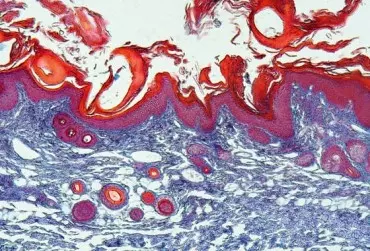

Świerzb jest wywoływanym przez świerzbowca ludzkiego zakażeniem pasożytniczym często występującym w populacji dziecięcej. W artykule przedstawiono epidemiologię, objawy, powikłania, kryteria rozpoznania świerzbu oraz postepowanie terapeutyczne za szczególnym uwzględnieniem populacji pediatrycznej. Zastosowania skojarzonego postępowania farmakologicznego, higienicznego i środowiskowego jest konieczne, aby zapobiec zakażeniu osób z otoczenia chorego oraz wystąpieniu powikłań.